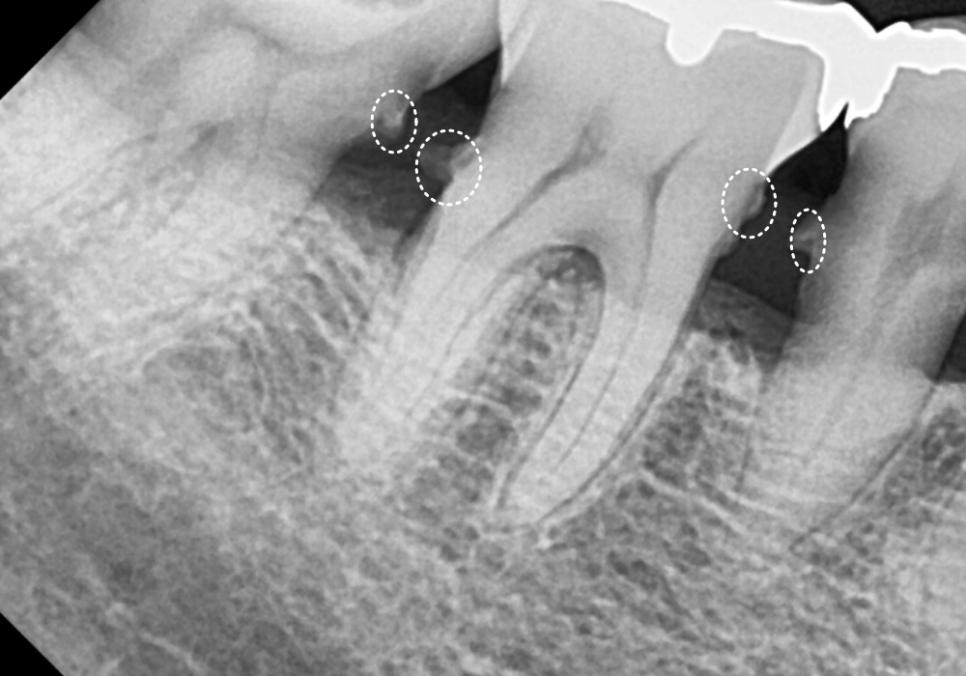

방사선 사진을 살펴볼게요~

매끈해보여야 할 치아 뿌리 쪽에

돌기처럼 무언가 붙어있는게 보이시나요?

251201

바로 치석인데요.

사실 치석은 밀도가 낮아

방사선 사진상에는

잘 나타나지 않는 경우가 많아요.

그런데 만약 엑스레이 사진에서

이처럼 치아 옆면이 매끄럽지 않고

돌기처럼 튀어나온 것이 보인다면,

정상적인 잇몸 상태 , 치아 뿌리 면이 매끄러움

치은연하치석이 뿌리면에 돌기처럼 붙어있는 모습

그건 치석이 이미 엄청나게

두껍고 단단하게 쌓였다는 뜻이에요..ㅜㅜ